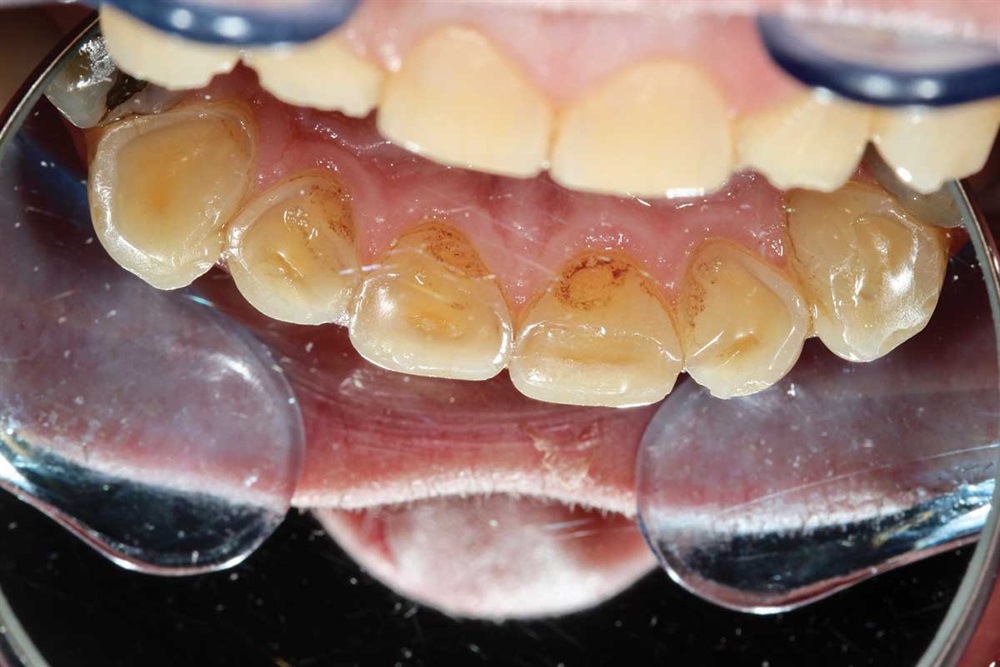

Show Your Work

Fig. 40: Plaque.

Fig. 41: Occlusion being adjusted. I did not increase his vertical when I did the upper teeth.

Fig. 42: Marks show heavier contact in lateral and protrusive excursions. Again, light occlusion on the centrals because of the lack of support I was bonding to.